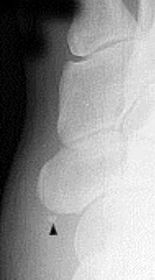

What is this? Where is it typically found? | Os interphalangeus. Typically found on the inferior aspect of the hallux IPJ. It is rare to see this ossicle at the IPJs of the lesser toes. |